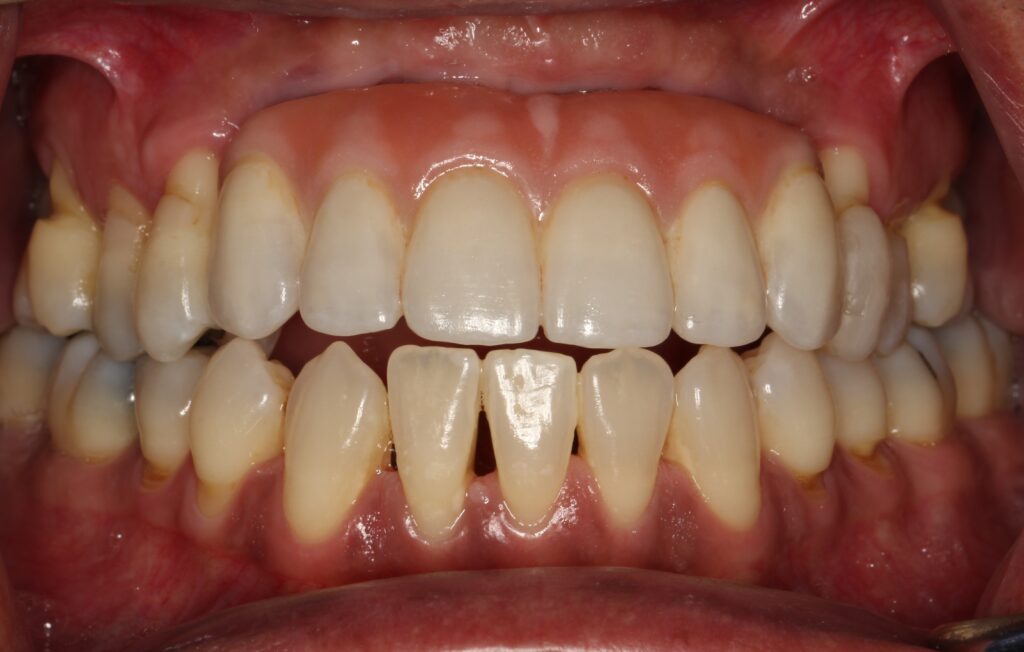

A selection of partial arch fixed implant bridge patients